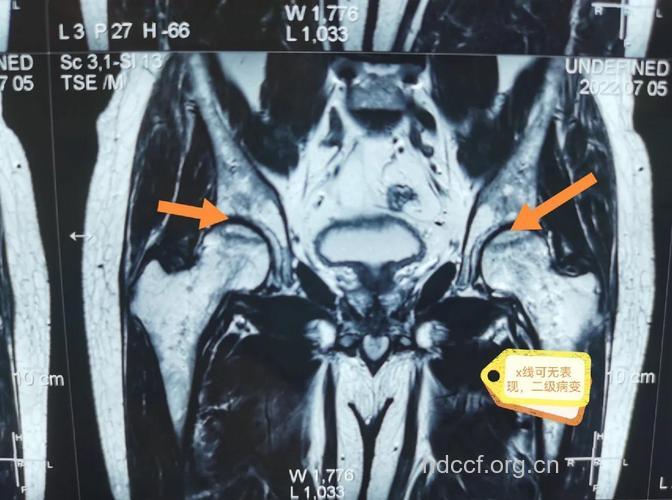

Ⅰ期 股骨头不变形,关节间隙正常,X 线平片、CT多不能显示明显的骨质病变,称X线前期。T1加权股骨头负重区(根据关节软骨结构和功能的特点,将股骨头软骨面分为三个部份,外上方与髋臼软骨面相差的压力负重区、压力负重区内侧的非压力负重区和外侧周围的非压力负重区)显示线样低信号。T 2 加权呈高信号病理特征,是骨和骨髓的坏死无修复,以骨髓水肿、骨细胞坏死、骨陷窝空虚为主要改变。

Ⅱ期 股骨头不变形,关节间隙正常。T 1加权为新月形边界清楚的不均匀信号,T 2加权显中等稍高信号,周围不均匀稍低信号环绕,呈典型的双线征,位置基本与CT的条状骨硬化一致。病理上为病灶中心大量不规则的细胞碎片坏死,周边纤维化,新骨形成和肉芽组织增生。